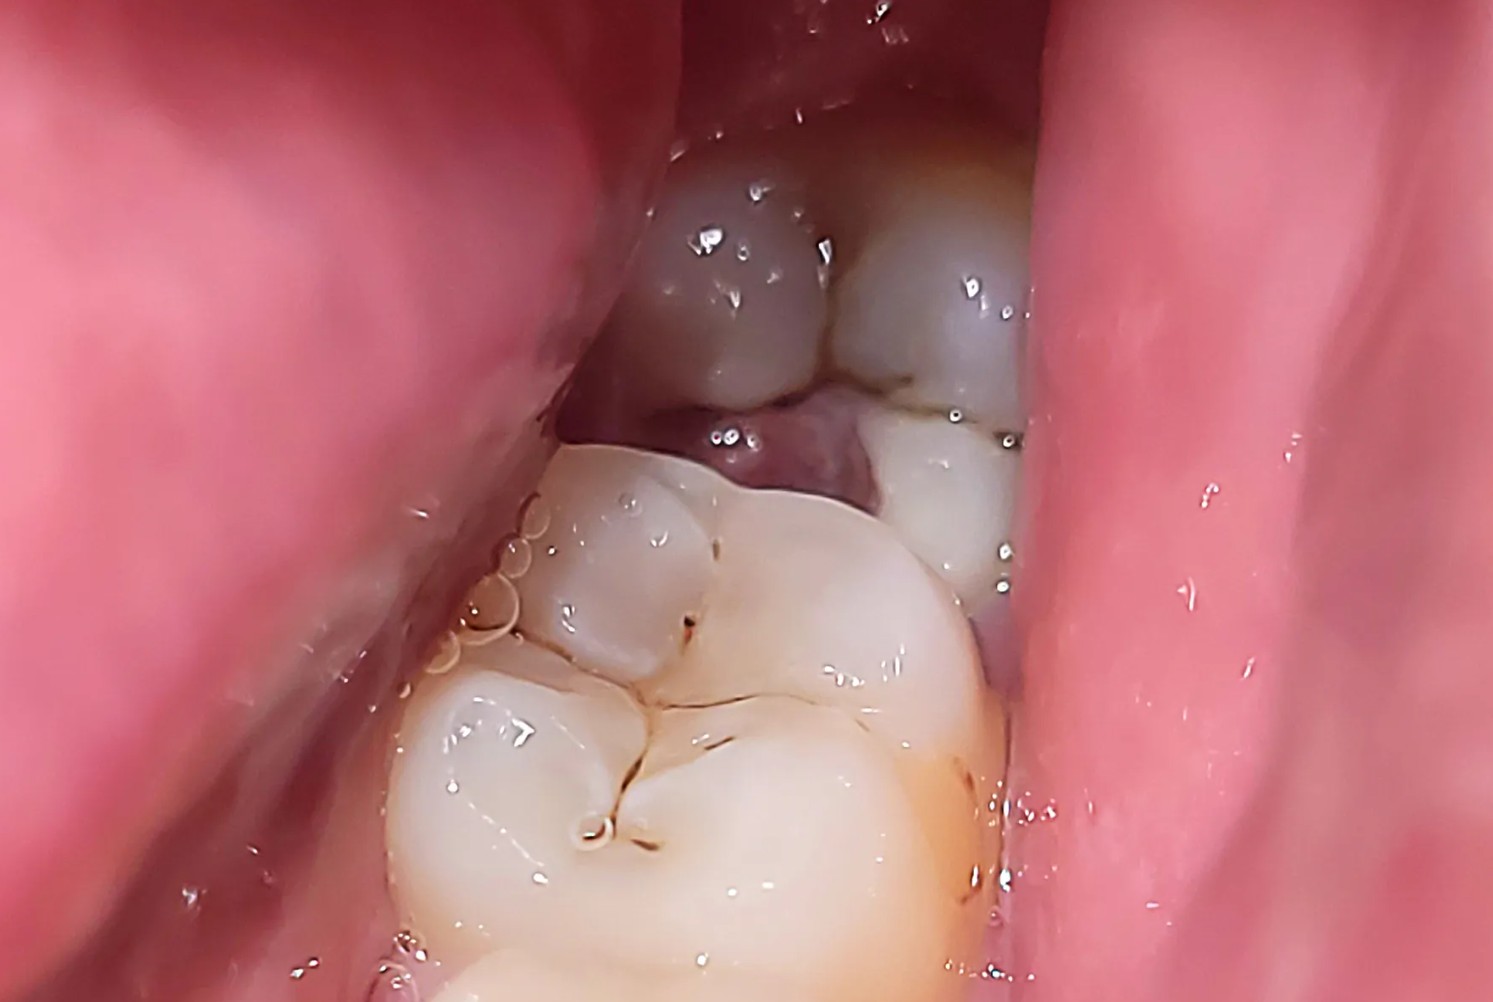

Răng khôn mọc ngầm là tình trạng răng khôn không thể trồi lên khỏi nướu như bình thường, mà bị “mắc kẹt” hoàn toàn hoặc một phần trong xương hàm. Do không đủ khoảng trống để mọc đúng hướng, răng khôn bị lệch hoặc chèn ép sang các răng bên cạnh, gây đau nhức và biến chứng.

- Mọc lệch: răng trồi lên khỏi nướu nhưng nghiêng sang bên.

- Mọc kẹt: một phần răng bị nướu hoặc xương che phủ.

- Mọc ngầm: răng nằm hoàn toàn trong xương, không trồi lên được.

Về mặt hình thái, răng khôn mọc ngầm có thể nằm ngang, chéo, ngược hoặc thẳng nhưng bị kẹt trong xương hàm. Trên phim X-quang, bác sĩ có thể dễ dàng nhận ra vị trí và hướng mọc của răng.